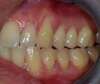

CAS GENCIVE  n°2

DOUBLE GREFFE GINGIVALE  SECTORIELLE (haut + bas)

intérêt santé + confort + esthétique